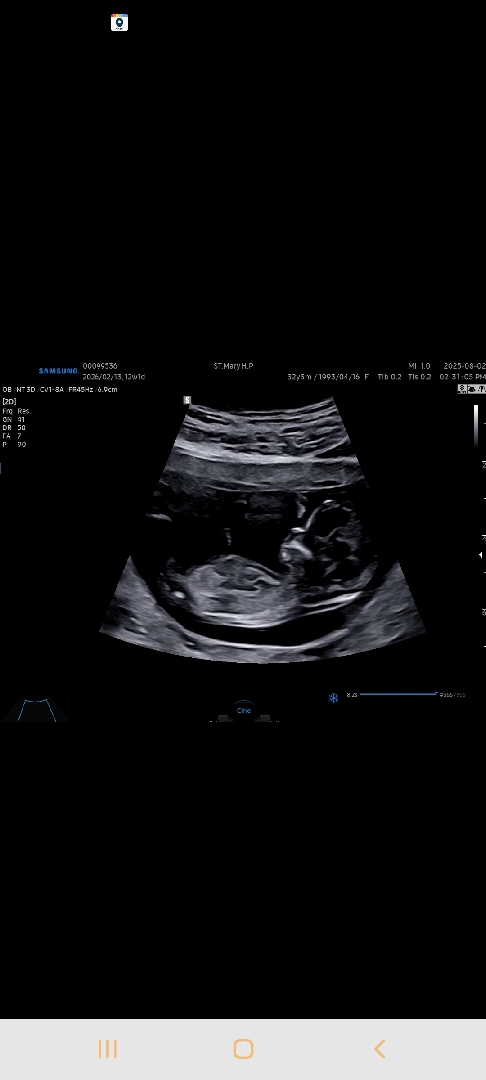

12주차2일차♡성별예측 가능할까요?!

사진이 뒤에가 애매한데 가능할까요???♡♡